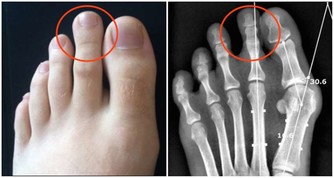

• 胳膊發麻:趴著睡,還可能壓到胳膊的神經或血管,引起手麻、無力。有人因此損傷了手臂上的橈神經,有人因此手臂畸形......

• 脊椎“變形”:當人趴著睡時,脊椎被迫彎成“C”字型,從而使腰椎、胸椎、頸椎呈非正常的生理曲度,這樣不僅會造成腰酸脖子痛,時間久了還可能誘發頸椎病、椎間盤突出。